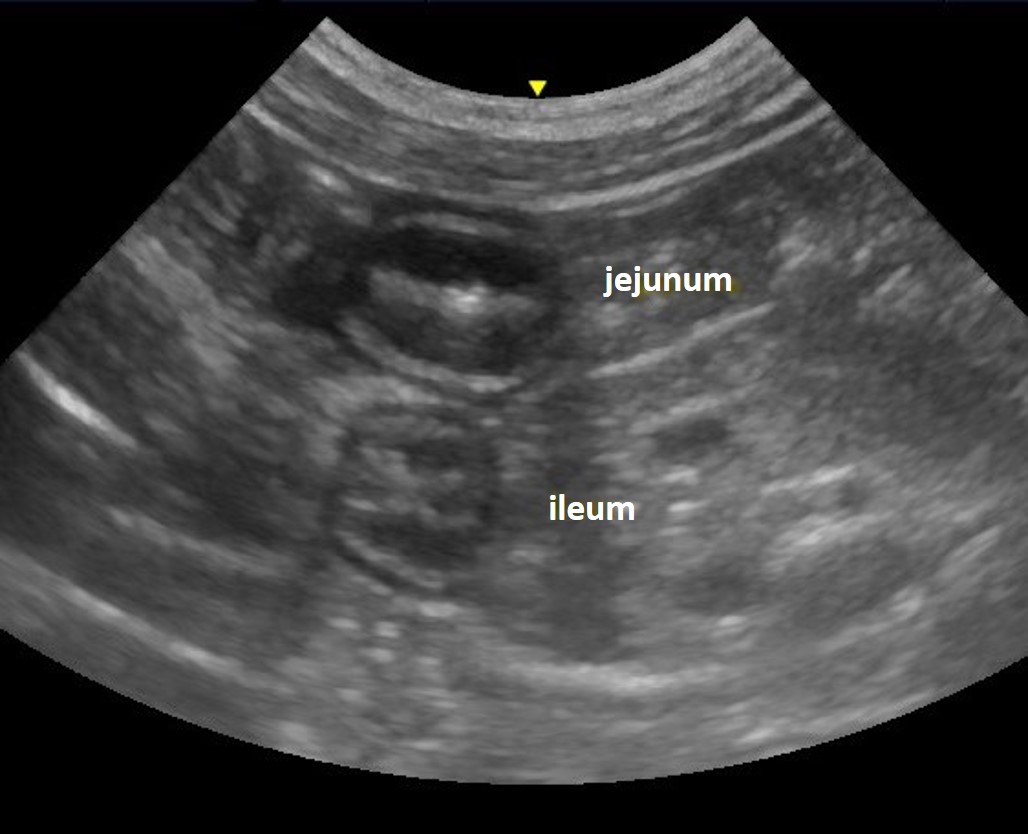

Jejunum

Jejunal loops can be visualised throughout the abdomen. Motility ranges from 1-3 peristaltic contractions per minute. 3

Ileum

The ileum is most readily identified using a right lateral approach. The prominent submucosa and contracted state give the lumen a star shape or rosetted, sphincter-like appearance (Figure 6). Although commonly found in cats, the ileo-caeco-colic junction is more rarely visualised in dogs, likely due to the presence of gas in the colon or caecum.5

Figure 6. Ileum – The ileum and a loop of jejunum are imaged in cross section in the same image. Note the difference in the appearance of the lumens; a rosette or star shaped appearance in the ileum, compared to a more linear appearance in the jejunum. The submucosa has a more pronounced and hyperechoic appearance in the ileum.